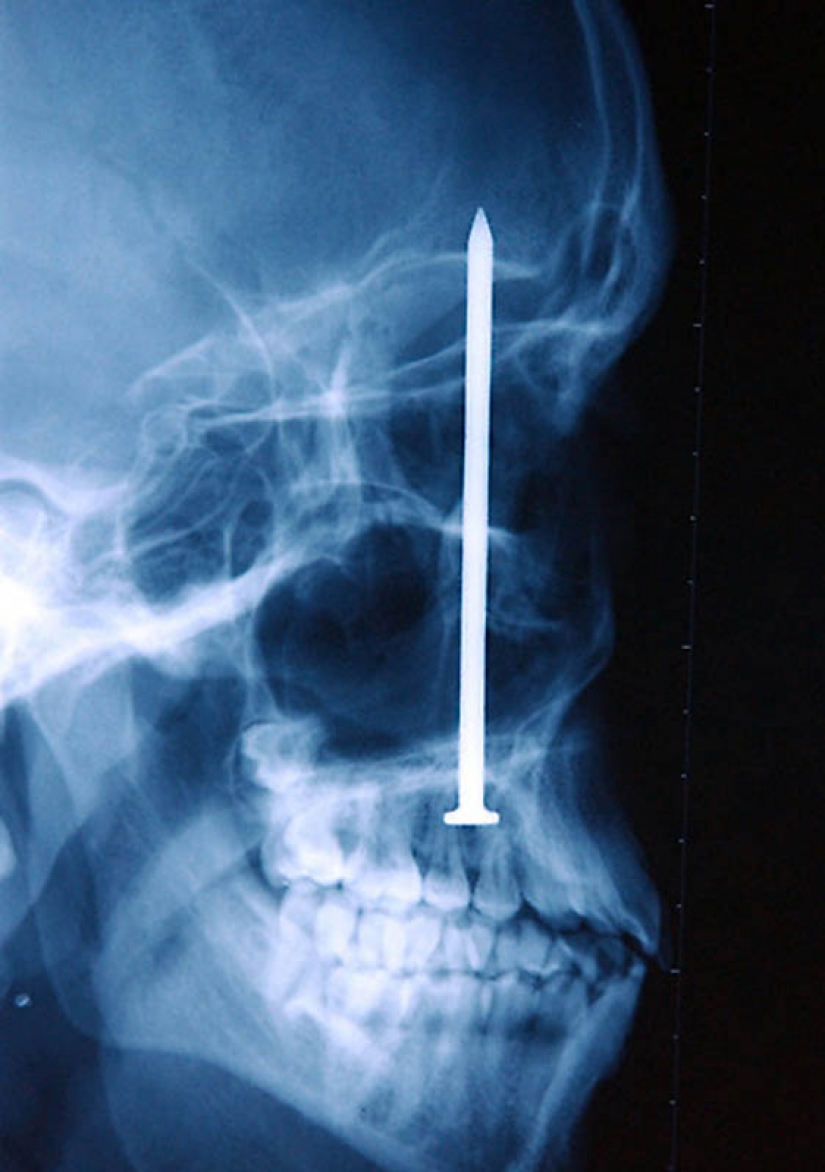

13. The nail in the human skull – the patient accidentally shot himself with a pneumatic hammer. He didn't even know that shot himself with a 10 – meter nail was found only after 6 days.